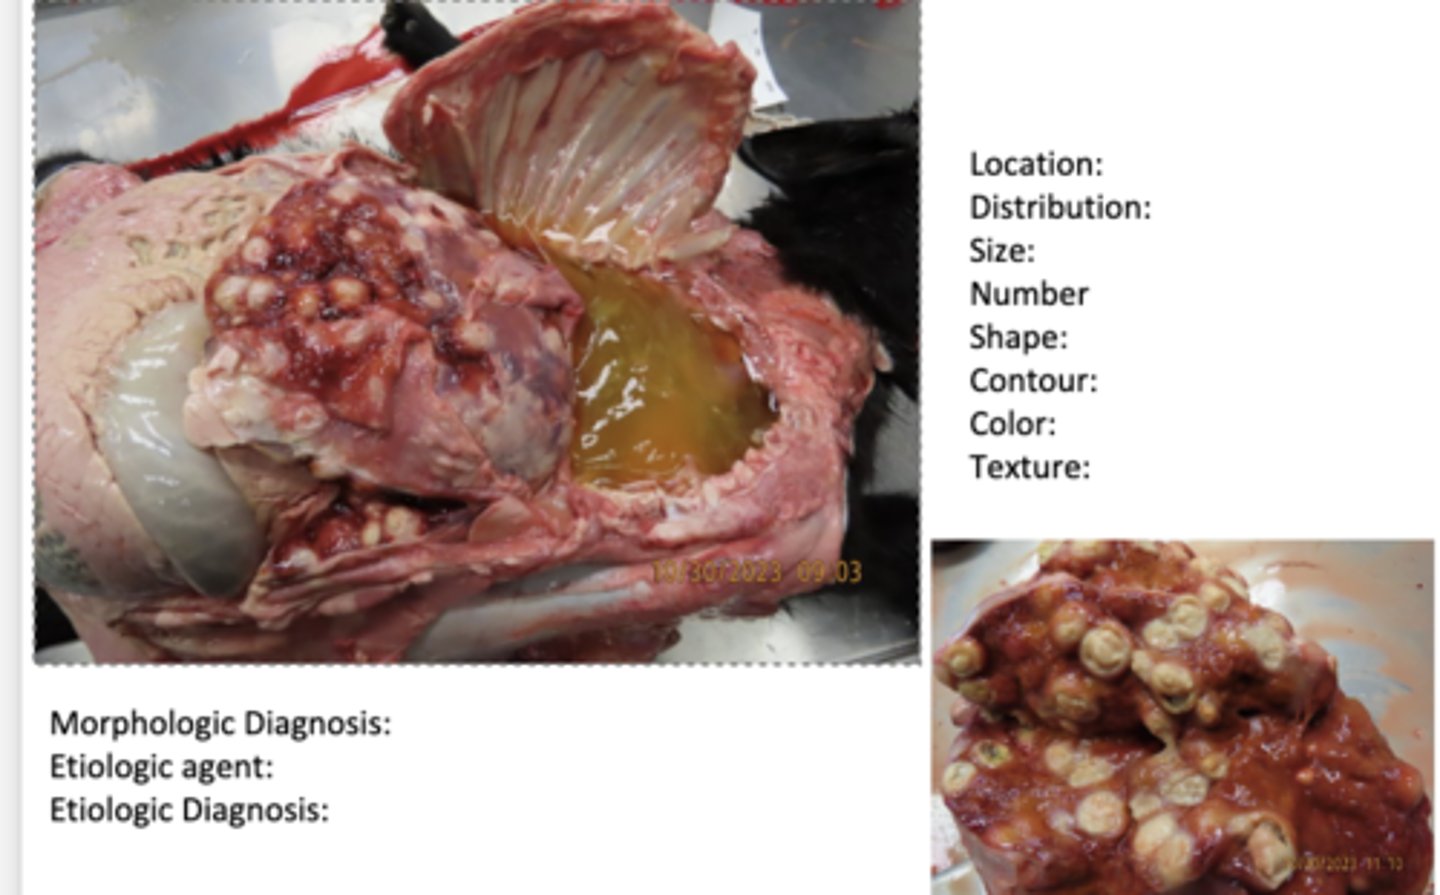

severe chronic active multifocal hepatic pylogranuloma from rhodococcus equi

Describe these lesions in this goat.